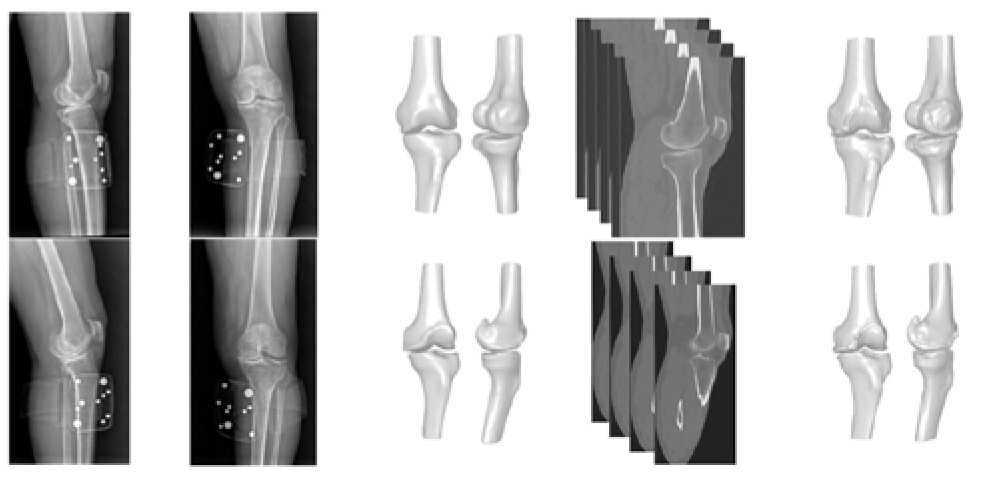

Validating a Novel 2D to 3D Knee Reconstruction Method on Preoperative Total Knee Arthroplasty Patient Anatomies

2. Materials and Methods